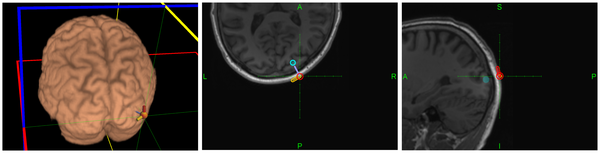

ขอขอบคุณภาพประกอบจาก plosone.org

งานวิจัยชิ้นนี้ได้รับการสนับสนุนจากนักวิจัยจากนานาชาติ โดยได้เผยแพร่ผลสำเร็จของชิ้นงาน เครื่องส่งสัญญาณสมองไฟฟ้าทางไกล หรือ EGG (Electroencephalography) ลงในวารสาร POLS ONE เมื่อวันที่ 19 สิงหาคม 2557 การทดลองในเบื้องต้นสำเร็จลุล่วงเป็นอย่างดี จากการสื่อสารระหว่างผู้ทดลอง 2 คน ในประเทศอินเดียและฝรั่งเศส โดยส่งสารเป็นคำว่า "hola" และ "ciao"

ในการสื่อสารได้ทำการแปะอิเล็กโทรดเพื่อจับสัญญาณคลื่นสมองของผู้ส่งสาร จากนั้นเครื่องทำการแปลงเป็นสัญญาณไบนารี่แล้วส่งไปยังเครื่่องรับปลายทาง ซึ่งทำการแปลงสัญญาณไบนารี่นั้นกลับเป็นสัญญาณไฟฟ้าอีกครั้ง แล้วกระตุ้นผ่านลูกตาในรูปสัญญาณแสงไปสู่สมอง ซึ่งรับรู้และตีสัญญาณนั้นเป็นข้อความตามที่ส่งมาได้ถูกต้อง